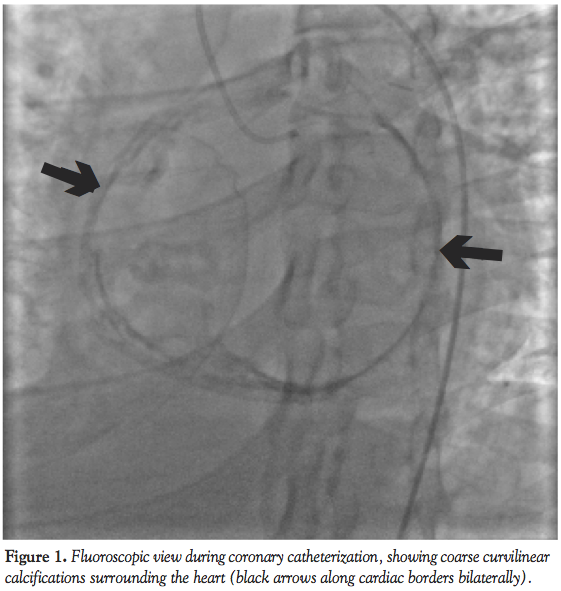

Case report. A 24-year-old woman was admitted to our hospital with progressive retrosternal chest pain, exertional dyspnea, tachycardia, and bilateral leg edema, persisting for 4 weeks. She had previous repair of coarctation of the aorta by left thoracotomy at age 13. Her blood pressure was 110/75 mm Hg, and her heart rate was 87 bpm. The physical examination was remarkable for mild jugular venous distension and pericardial knock. Liver function tests, electrolyte levels, cardiac enzymes, coagulation parameters, and urinalysis were within normal limits. Her ECG showed normal sinus rhythm, rightward axis, and intraventricular conduction delay. Chest x-ray revealed mediastinal enlargement with mild cardiomegaly, pericardial calcification, and right pleural effusion. Two-dimensional echocardiography demonstrated enhanced echogenicity of the pericardium suggesting the presence of calcification, biatrial enlargement, normal left ventricular dimensions, and systolic function (ejection fraction 59%), and abnormal ventricular septal motion. Cardiovascular magnetic resonance imaging confirmed pericardial thickening with calcification, presence of constrictive physiology with septal bounce, and abrupt cessation of left ventricle diastolic filling. Cardiac catheterization revealed equalization of end-diastolic pressures, and interdependence of ventricular pressures consistent with constrictive physiology. Coronary angiogram demonstrated the obliteration of the second obtuse marginal branch of left circumflex artery in systole and diastole, and compression of the first obtuse marginal branch that induced mid to late diastolic interruption of coronary flow (Video). The patient was referred to surgery and pericardiectomy was performed. Histopathologic examination of the pericardium excluded mycobacterium tuberculosis or granulomatous diseases. The patient was discharged home following surgery and her symptoms were improved during the postoperative follow-up.

Discussion. We describe here a case of constrictive pericarditis associated with compression of the first and second obtuse marginal branch of circumflex coronary artery. Compression of coronary arteries with pericardial constriction is an unusual condition. Our case represents an unusual presentation with angina pectoris and signs and symptoms of myocardial ischemia along with right heart failure. Angina can be related to a calcification originating from the pericardium and constraining the coronary artery, or due to diastolic filling of the left ventricle that compresses the vessel against the fixed noncompliant pericardium.

Goldberg et al described a patient with tuberculous pericarditis who had complete obliteration of an obtuse marginal branch of the left circumflex artery, due to pericardial calcification infiltrating the coronary artery.11 Ours and Goldberg’s case underline the importance of the timing of the compression of the coronary vessel during the cardiac cycle. Diastolic stenosis of coronary arteries is suggestive of external compression rather than arterial obliteration. On the other hand, diastolic compression of coronary artery is not a specific sign of constrictive pericarditis, since it has also been reported in patients with increased diastolic ventricular pressure.5,6 The coronary flow pattern can distinguish the underlying etiology of coronary compression. If the compression begins early in diastole, this finding suggests increased intraventricular pressures. On the other hand, if the compression of the coronary artery occurs in mid to late diastole, it suggests decreased compliance of the overlying pericardium. In the case presented here, the relief of diastolic compression after pericardiectomy and the presence of prevalent compression of coronary artery during mid-late diastole were suggestive of pericardial constriction. We conclude that angiographic demonstration of native coronary artery compression in the presence of right heart failure symptoms can suggest pericardial constriction, and the compression of the coronary artery in mid to late diastole might be a specific sign of pericardial constriction. Once a diagnosis is made, extensive resection of the pericardium rather than partial decortication limited to the anterior and lateral surface of the ventricles is mandatory to avoid recurrence of pericardial constriction following surgery. Several reports in the literature12,13 support this strategy of treatment as they revealed recurrent pericardial constriction following partial pericardiectomy with residual pericardium in the posterior surface of the heart.